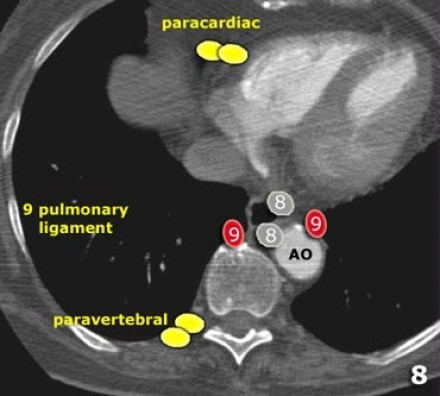

9. Linfonodos do ligamento Pulmonar

Linfonodos do ligamento pulmonar estão dentro do ligamento pulmonar, incluindo aqueles na parede posterior e inferior da veia pulmonar inferior.

O ligamento pulmonar é a extensão inferior das reflexões da pleura mediastinal que cercam o hilos.

9. Ligamento pulmonar: linfonodos que se encontram no ligamento pulmonar.